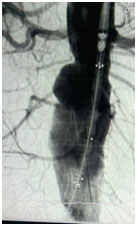

6th Oct 2017: It gives us pride & pleasure to announce that, the first ever procedure EVAR (endovascular aortic repair) has been done in Dr. Ziauddin Hospital (Clifton campus), under the team members;

Dr. Kamal Yusuf, Dr. Muhammad Ali and Dr. Ameer from Jordan played the key role in managing the whole process.